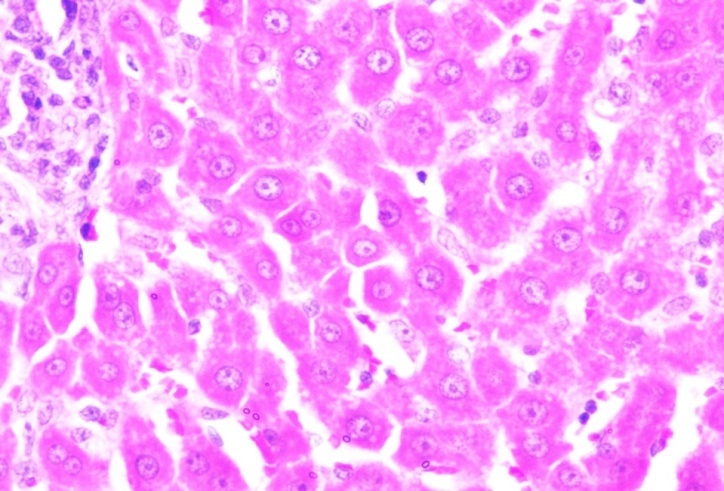

Histopathological results (Animal liver) (fig. 20)

Normal control |

Cancer control |

| Section show structure of liver with sheets of hepatocytes separated by sinusoids cartial vein and portal tract appear normal | Section shows the structure of liver presented hepatic congestion at sinusoids and the portal vessel, pericentre globular micro-steatosis, kuffe cell proliferation, diffuse hepatocyte necrosis and mononuclear infiltrate |

Positive control |

Treatment control-FMCuNPs |

| Section show structure of liver presented mild hepatic congestion at sinusoids and the portal vessel, pericentre globular micro-steatosis, no kuffe cell proliferation, mild hepatocyte diffuse necrosis and mononuclear infiltrate. | Section show structure of liver presented moderate hepatic congestion at sinusoids and the portal vessel, pericentre globular micro-steatosis, less kuffe cell proliferation, mild hepatocyte diffuse necrosis and mononuclear infiltrate. |

Fig. 20: Histopathological images of the animal liver in vivo anticancer activity of FMCuNPs